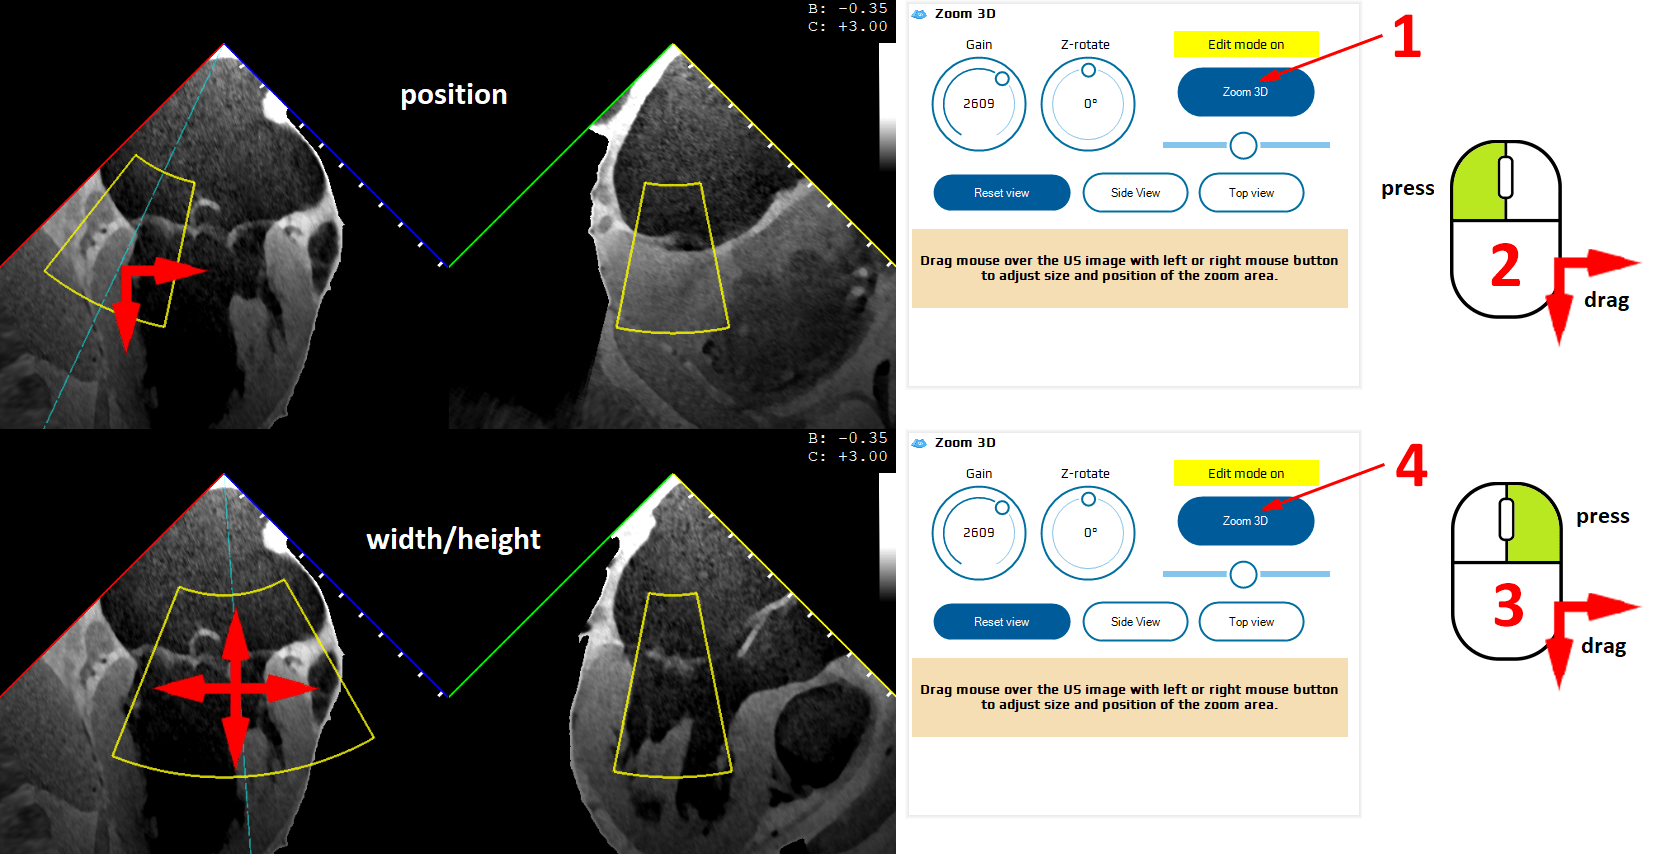

3D mode

Clicking the Zoom 3D button (Fig. 9. Nr 1) activates two boxes that let the user select the region of interest (ROI) on both xPlane views, using a mouse (Fig. 9. Nr 2 and 3).

The second click on the Zoom 3D button (Fig. 9. Nr 4) switches on the 3D rendering function.

The Gain should be adjusted (usually, initially significantly decreased) to optimally visualize the cardiac structures. Z rotation is used to rotate the model on the screen (Z axis being perpendicular to the screen).

The 3D volume can be rotated (X and Y axes) by dragging the mouse.